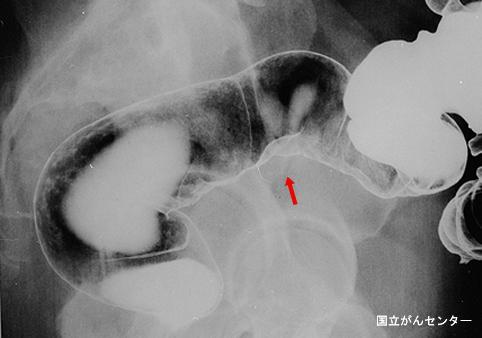

A case of malignant mucocele of the appendix with peudomixoma peritonei.

Appendix/Mucinous cystadenocarcinoma

Location

Technique, Method

25 - 29